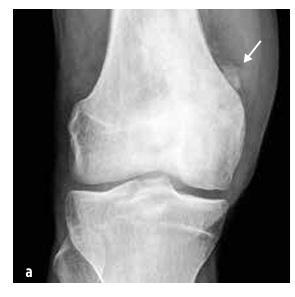

Gyermekkori előfordulása leggyakrabban osteosarcoma (55%, lásd az 5. ábrát) és Ewing-szarkóma (35%, lásd a 6. ábrát), a chondrosarcoma rendkívül ritka. Ebbe a csoportba tartoznak még a lágyrész szarkómák (rabdomioszarkóma és nem-rabdomioszarkómák), a mezenchimális sejtekből származó tumorok, az extraszkeletális Ewing-szarkóma, a szinoviális szarkóma, a fibroszarkóma és az embrionális szarkóma.

5. ábra

Osteosarcoma a distalis femuris